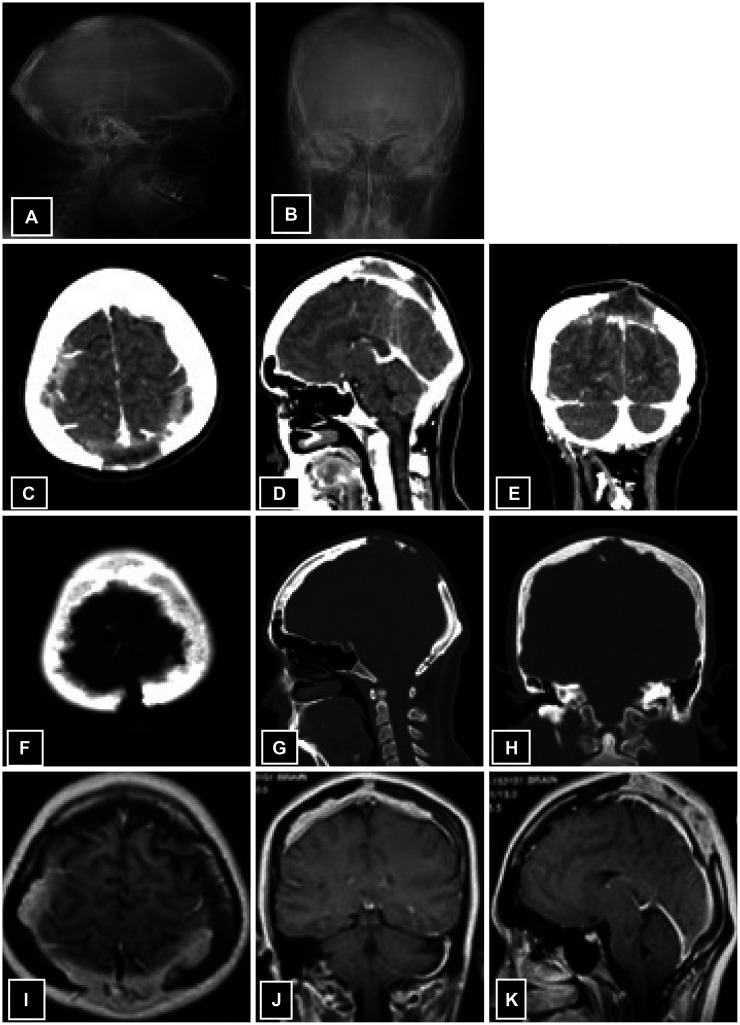

Langerhans cell histiocytosis (LCH) is a rare condition in adults, especially when it is limited to a single area of the skull, known as solitary calvarial involvement. In this case report, we present a unique instance of LCH affecting the parietal bone with a pus-draining fistula. This is a rare and unusual presentation at this location, which has been scarcely reported in medical literature. A 30-year-old woman with no prior comorbidity presented with complaints of headache that persisted for a year. She also had swelling on her scalp and a yellowish discharge for 3 weeks, but no neurological problems were observed. Radiology revealed thinning of the calvaria, with ragged margins along the inner table, multiple focal erosions, and involvement of overlying soft tissue and bony sequestrum. The patient underwent biparietal craniotomy and excision of the lesion. The histopathology report showed LCH. After 8 months of follow-up, there was no recurrence. The management of solitary calvarial involvement by LCH with masquerading presentation as a scalp infection can be achieved through complete excision of the lesions, resulting in a favorable outcome.